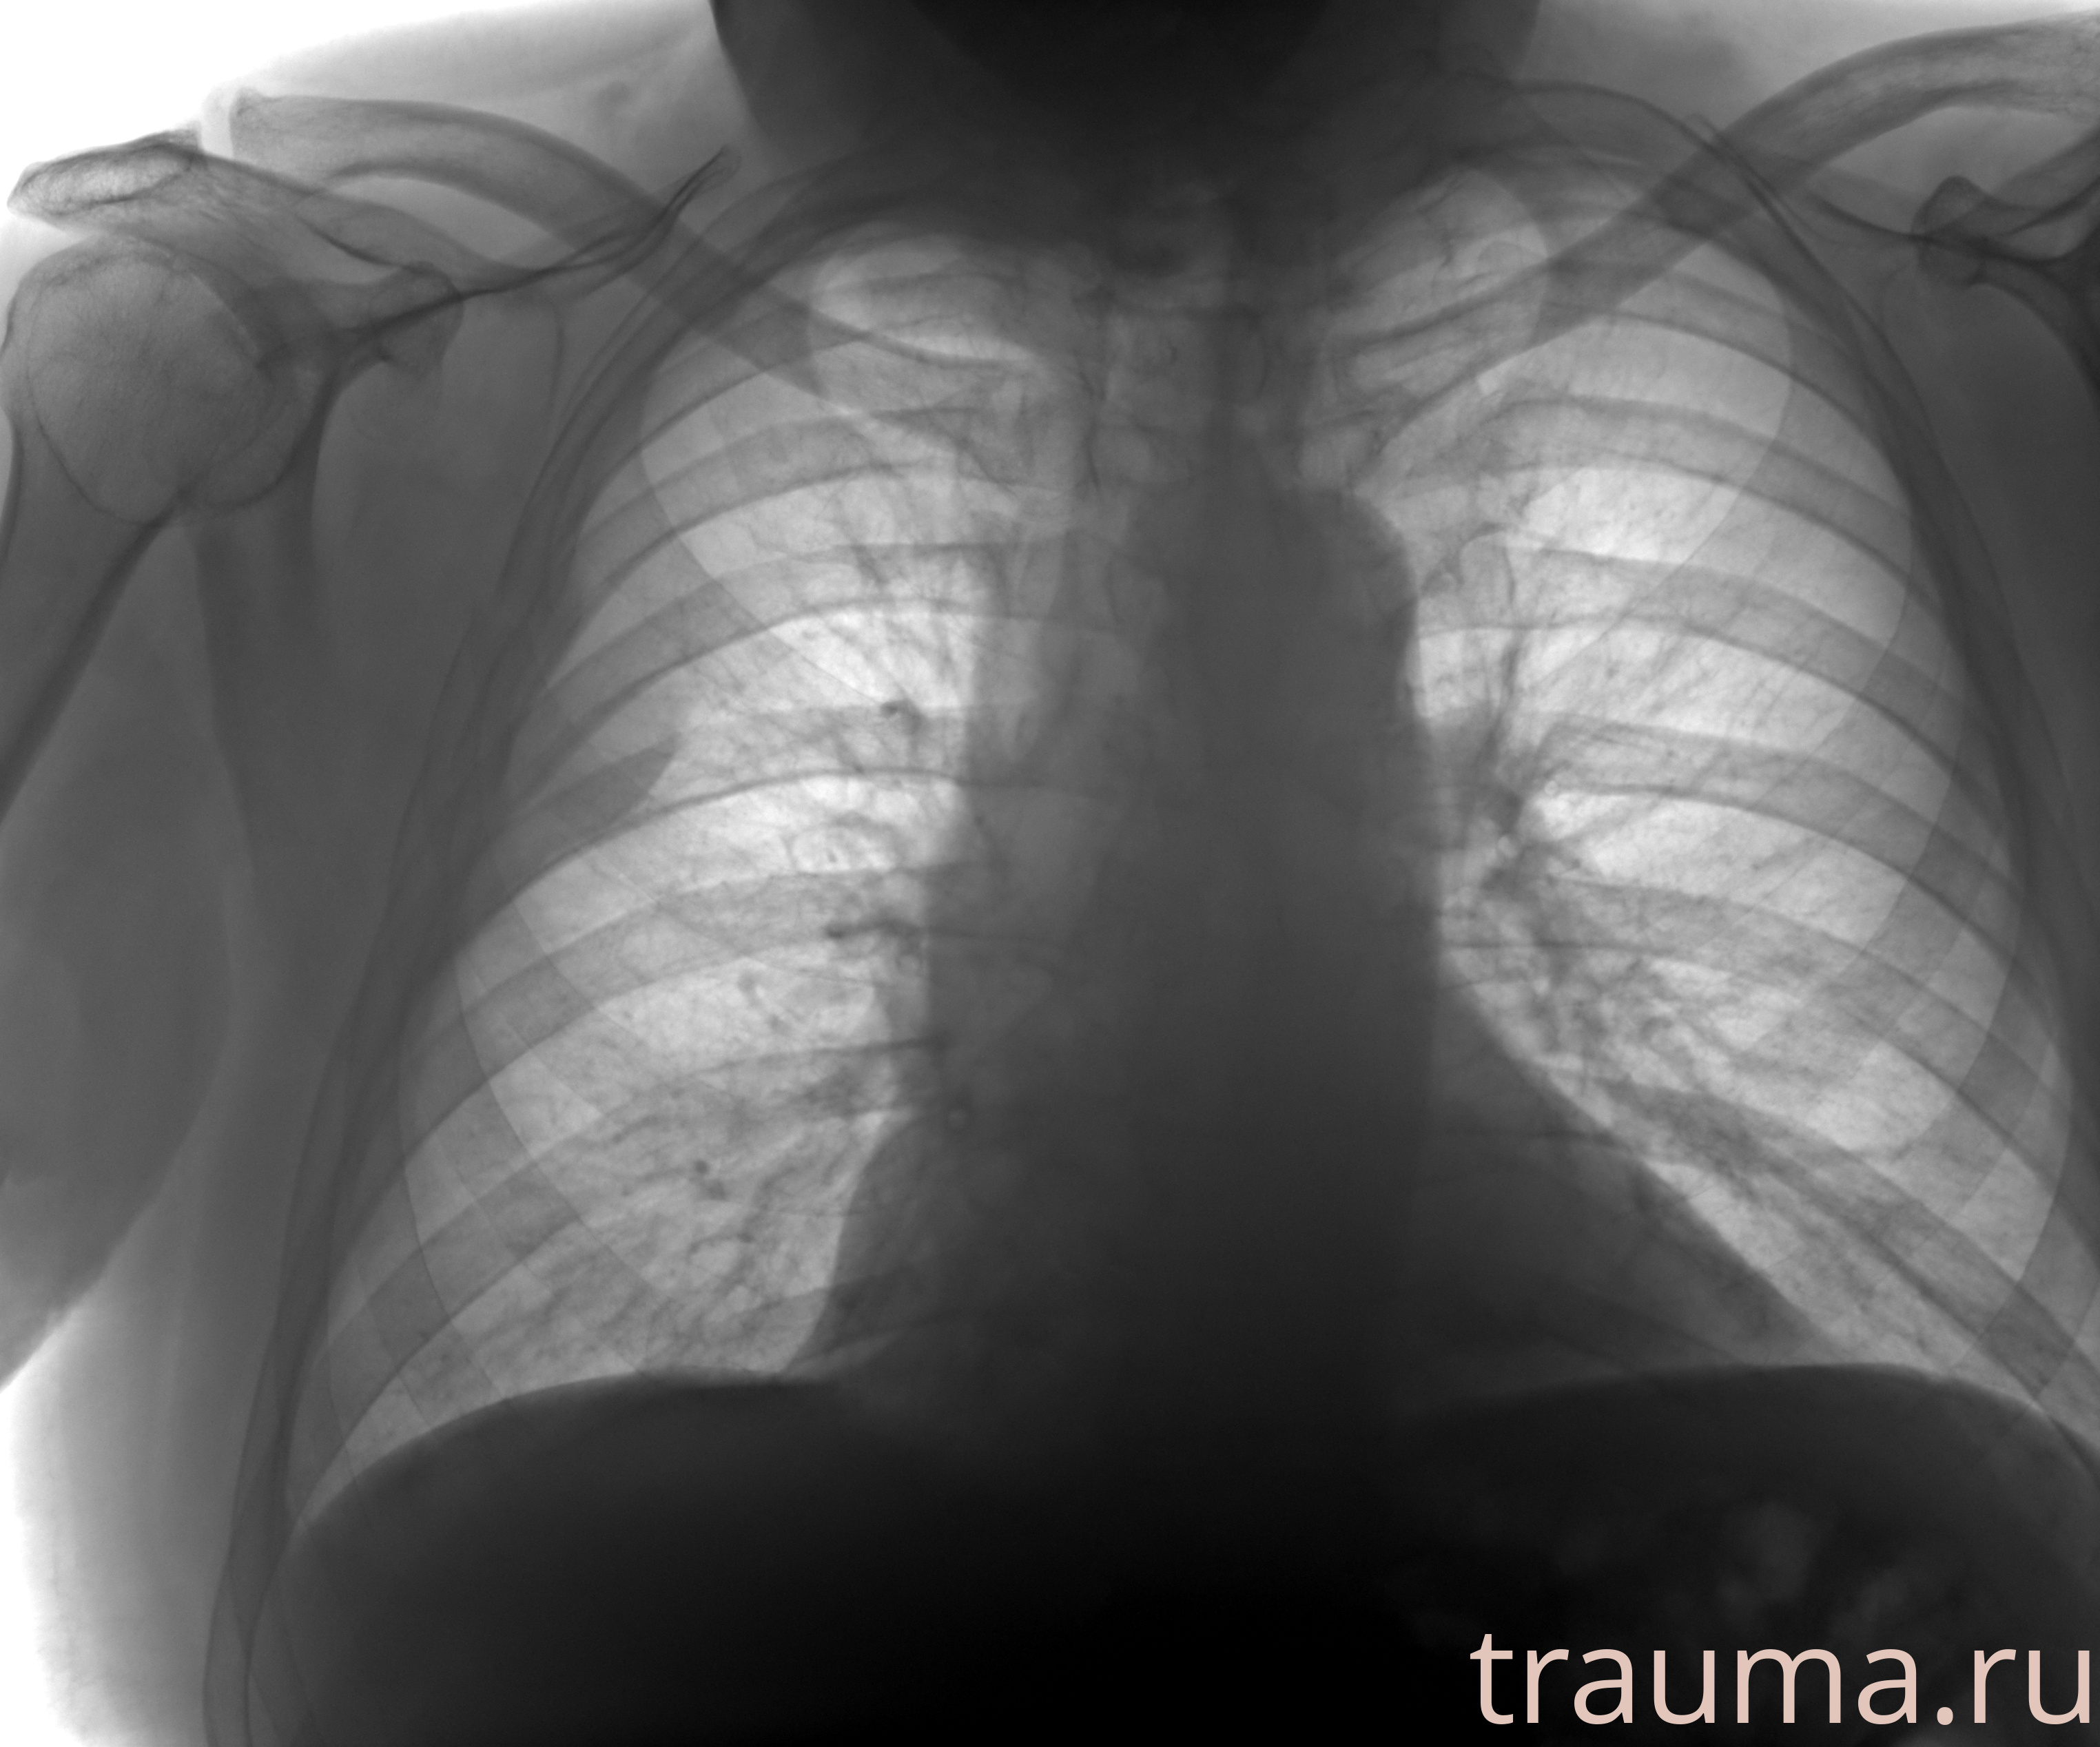

Рентген на дому: по вашему адресу приезжает врач-рентгенолог, травматолог-ортопед с мобильным рентгеновским аппаратом, проводит диагностику травмы или заболевания, делает необходимые рентгенограммы, дает рекомендации по дальнейшему лечению. Получить качественные снимки в домашних условиях возможно благодаря уникальной методике, разработанной МосРентген Центром для института  Склифосовского